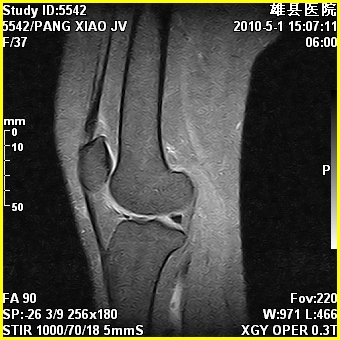

标题: MRI2894:患者右膝关节疼痛两月余,无明显外伤史 [打印本页]

标题: MRI2894:患者右膝关节疼痛两月余,无明显外伤史

右股骨下端前内侧类圆形异常信号,位于干骺端,呈长t1长t2改变,但信号不均,t1图上病灶中心见小片状稍高信号影,t2图上见散在稍低信号影,stir像呈高信号,因病灶较小,缺乏特征性改变,结合患者年龄及部位,考虑嗜酸性肉芽肿可能性大。胫骨关节面下的小囊状异常信号,如果一元论考虑则为嗜酸性肉芽肿,不过发生在这个部位的少见,二元论考虑为邻关节骨囊肿。半月板与前后交叉韧带均未见异常。

右股骨下端前内侧干骺端囊性良性病变,考虑 1内生软骨瘤 2骨囊肿 3肉芽肿。